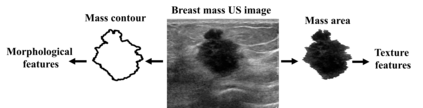

Standard classification methods based on handcrafted morphological and texture features have achieved good performance in breast mass differentiation in ultrasound (US). In comparison to deep neural networks, commonly perceived as "black-box" models, classical techniques are based on features that have well-understood medical and physical interpretation. However, classifiers based on morphological features commonly underperform in the presence of the shadowing artifact and ill-defined mass borders, while texture based classifiers may fail when the US image is too noisy. Therefore, in practice it would be beneficial to select the classification method based on the appearance of the particular US image. In this work, we develop a deep meta-network that can automatically process input breast mass US images and recommend whether to apply the shape or texture based classifier for the breast mass differentiation. Our preliminary results demonstrate that meta-learning techniques can be used to improve the performance of the standard classifiers based on handcrafted features. With the proposed meta-learning based approach, we achieved the area under the receiver operating characteristic curve of 0.95 and accuracy of 0.91.